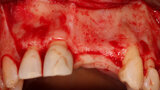

Fig. 17: The healed grafted ridge at 4.5 months following flap elevation demonstrating adequate width facial-palatally to allow implant placement.